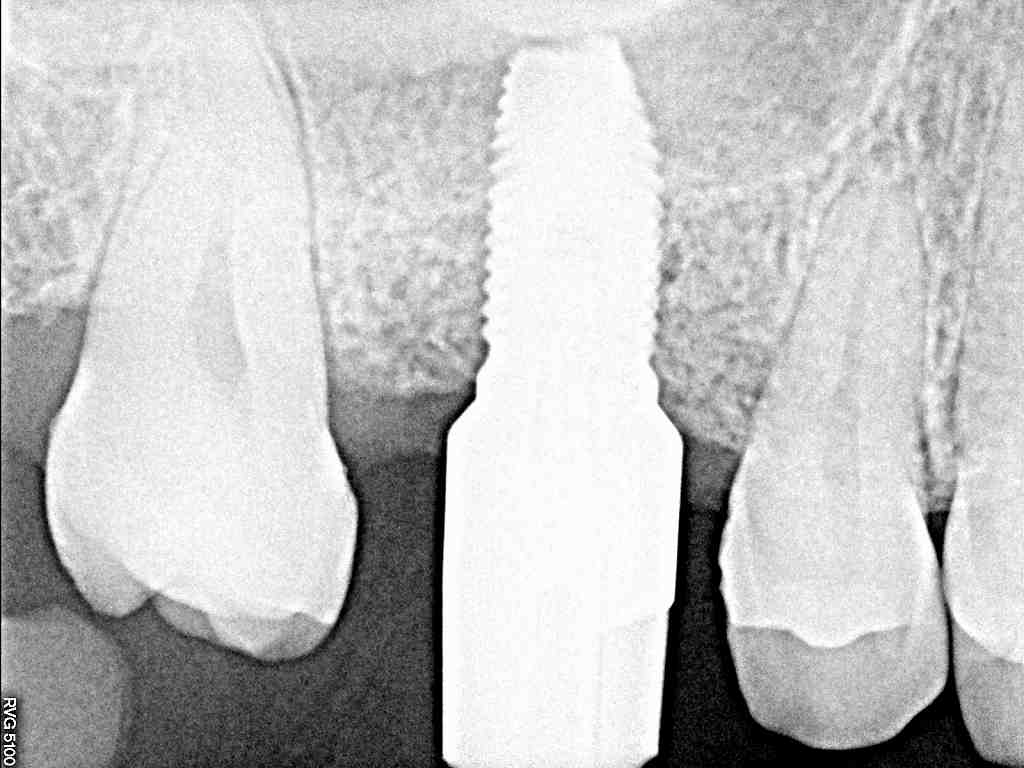

右上6番 上顎洞までの距離を測り抜歯即時インプラント埋入 インプラントは埋入時の位置取り、距離、角度を綿密に計算しながら埋入しなければなりません

右上6番 上顎洞までの距離を測り抜歯即時インプラント埋入 インプラントは埋入時の位置取り、距離、角度を綿密に計算しながら埋入しなければなりません

インプラントはシリコン印象にて精密に印象採取を行っていきます